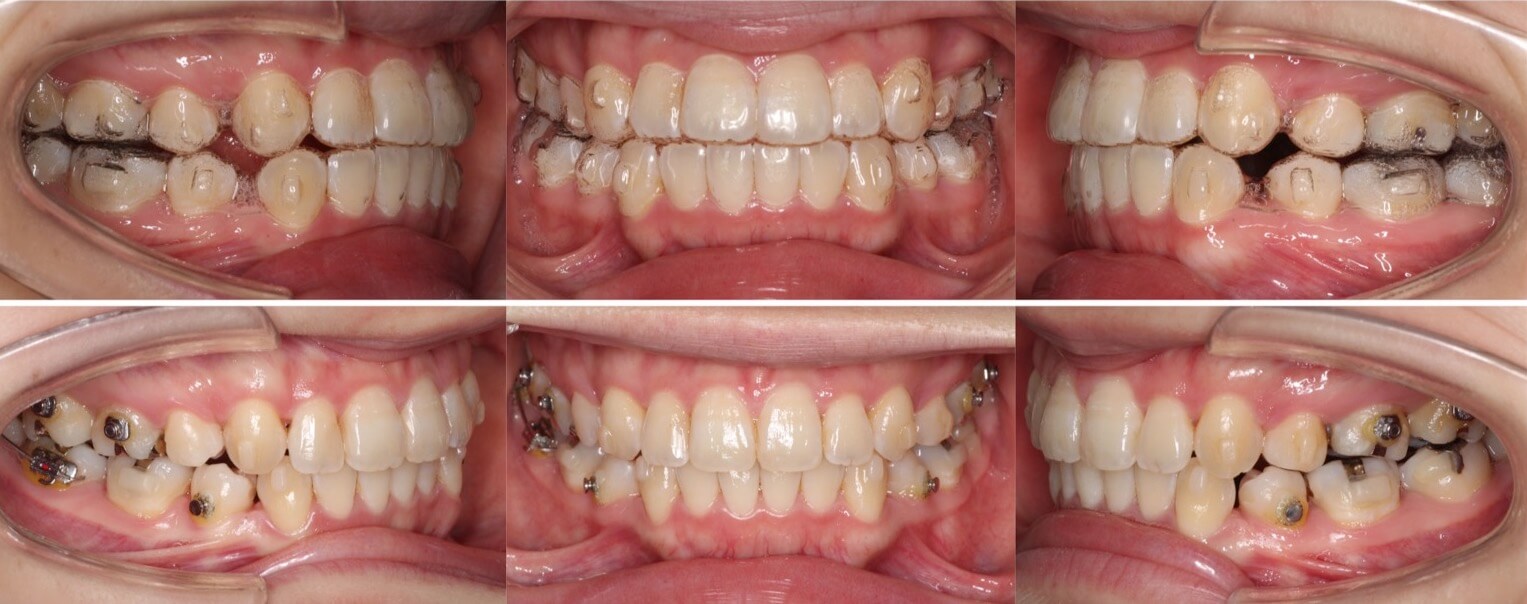

高校生女子・唇側矯正装置・前歯傾斜型

<顔のビフォーアフター>

<症例概要>

主訴:出っ歯とデコボコ

年齢・性別:高校生女子

住まい:千葉県八千代市

症状:叢生・上下顎前突

治療方針:抜歯空隙の閉鎖(最大固定)

治療装置:唇側矯正装置

固定装置:ナンスホールディングアーチ

抜歯:上下左右第一小臼歯抜歯(計4本)

治療期間:1年11か月

リテーナー:上プレートタイプ+下フィックスタイプ

治療費用:968,000(税込)

代表的副作用:痛み・治療後の後戻り・歯根吸収・歯髄壊死・歯肉退縮

上下の前歯が前方に傾斜しているため、口が閉じずらい上下顎前突症例です。しっかりと永久歯が生えるまでは、少しでも前歯を後方移動させるためのスペースを獲得するために半年ほどヘッドギア装置を使用しました。その後、小臼歯抜歯を併用し本格矯正治療を行い前歯を約8mmほど後方移動させました。治療後は口元の緊張感もなくなり、すっきりとした横顔になりました。